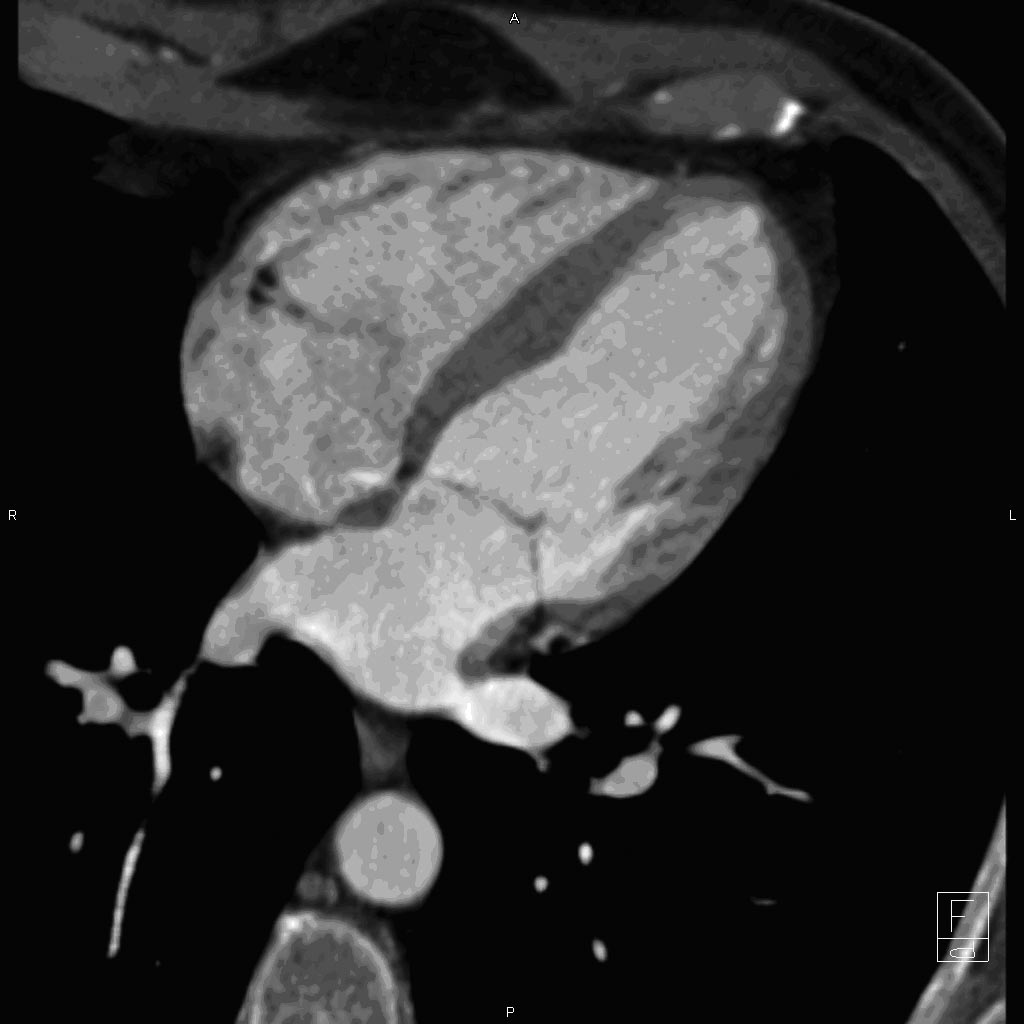

Maximize the Quality

of a Cardiac CT Study

The combination of Empower Phasing

Protocol (EPPTM) and the injector system

allows dual syringes to alternate between

contrast and a saline chase to help

maximize the quality of a cardiac CT study

1

Image 1 courtesy of Suhny Abbara, MD, Assistant Professor, Harvard Medical School, Director, Cardiovascular Imaging, Massachusetts General Hospital, Director of Education, Cardiac MR/PET/CT Program Image 2 and 3 courtesy of Orla Buckley MD, Andetta Hunsaker MD and Frank Rybicki MD, Brigham and Women's Hospital, Applied Imaging Science Laboratory, Department of Radiology

These are representative images from reference studies; individual results may vary.